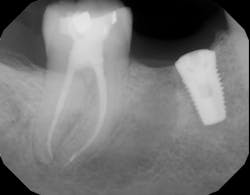

- The type of endodontic treatment dictates the length of healing. Nonsurgical endodontic treatment has a usual healing time of three months. Surgical intervention such as an apicoectomy due to large lesion size can take six to 12 months to heal (figures 1 and 2).

If definitive crown placement is delayed and the patient has excessive forces on the tooth or suffers from direct trauma, the tooth can fracture. In many cases, a decision must be made upon full bone healing versus the likelihood of crown fracture (figure 3–6). In addition, most studies show that full-coverage crowns are a main factor in determining long-term success of root canal therapy, with successes ranging from 92% for teeth receiving crowns compared to 35% for those not receiving crowns after a one- to five-year follow-up.2 In another study on molar teeth five years after root canal therapy, teeth that had crowns placed had a success rate of 78% versus 36% without crown coverage.3